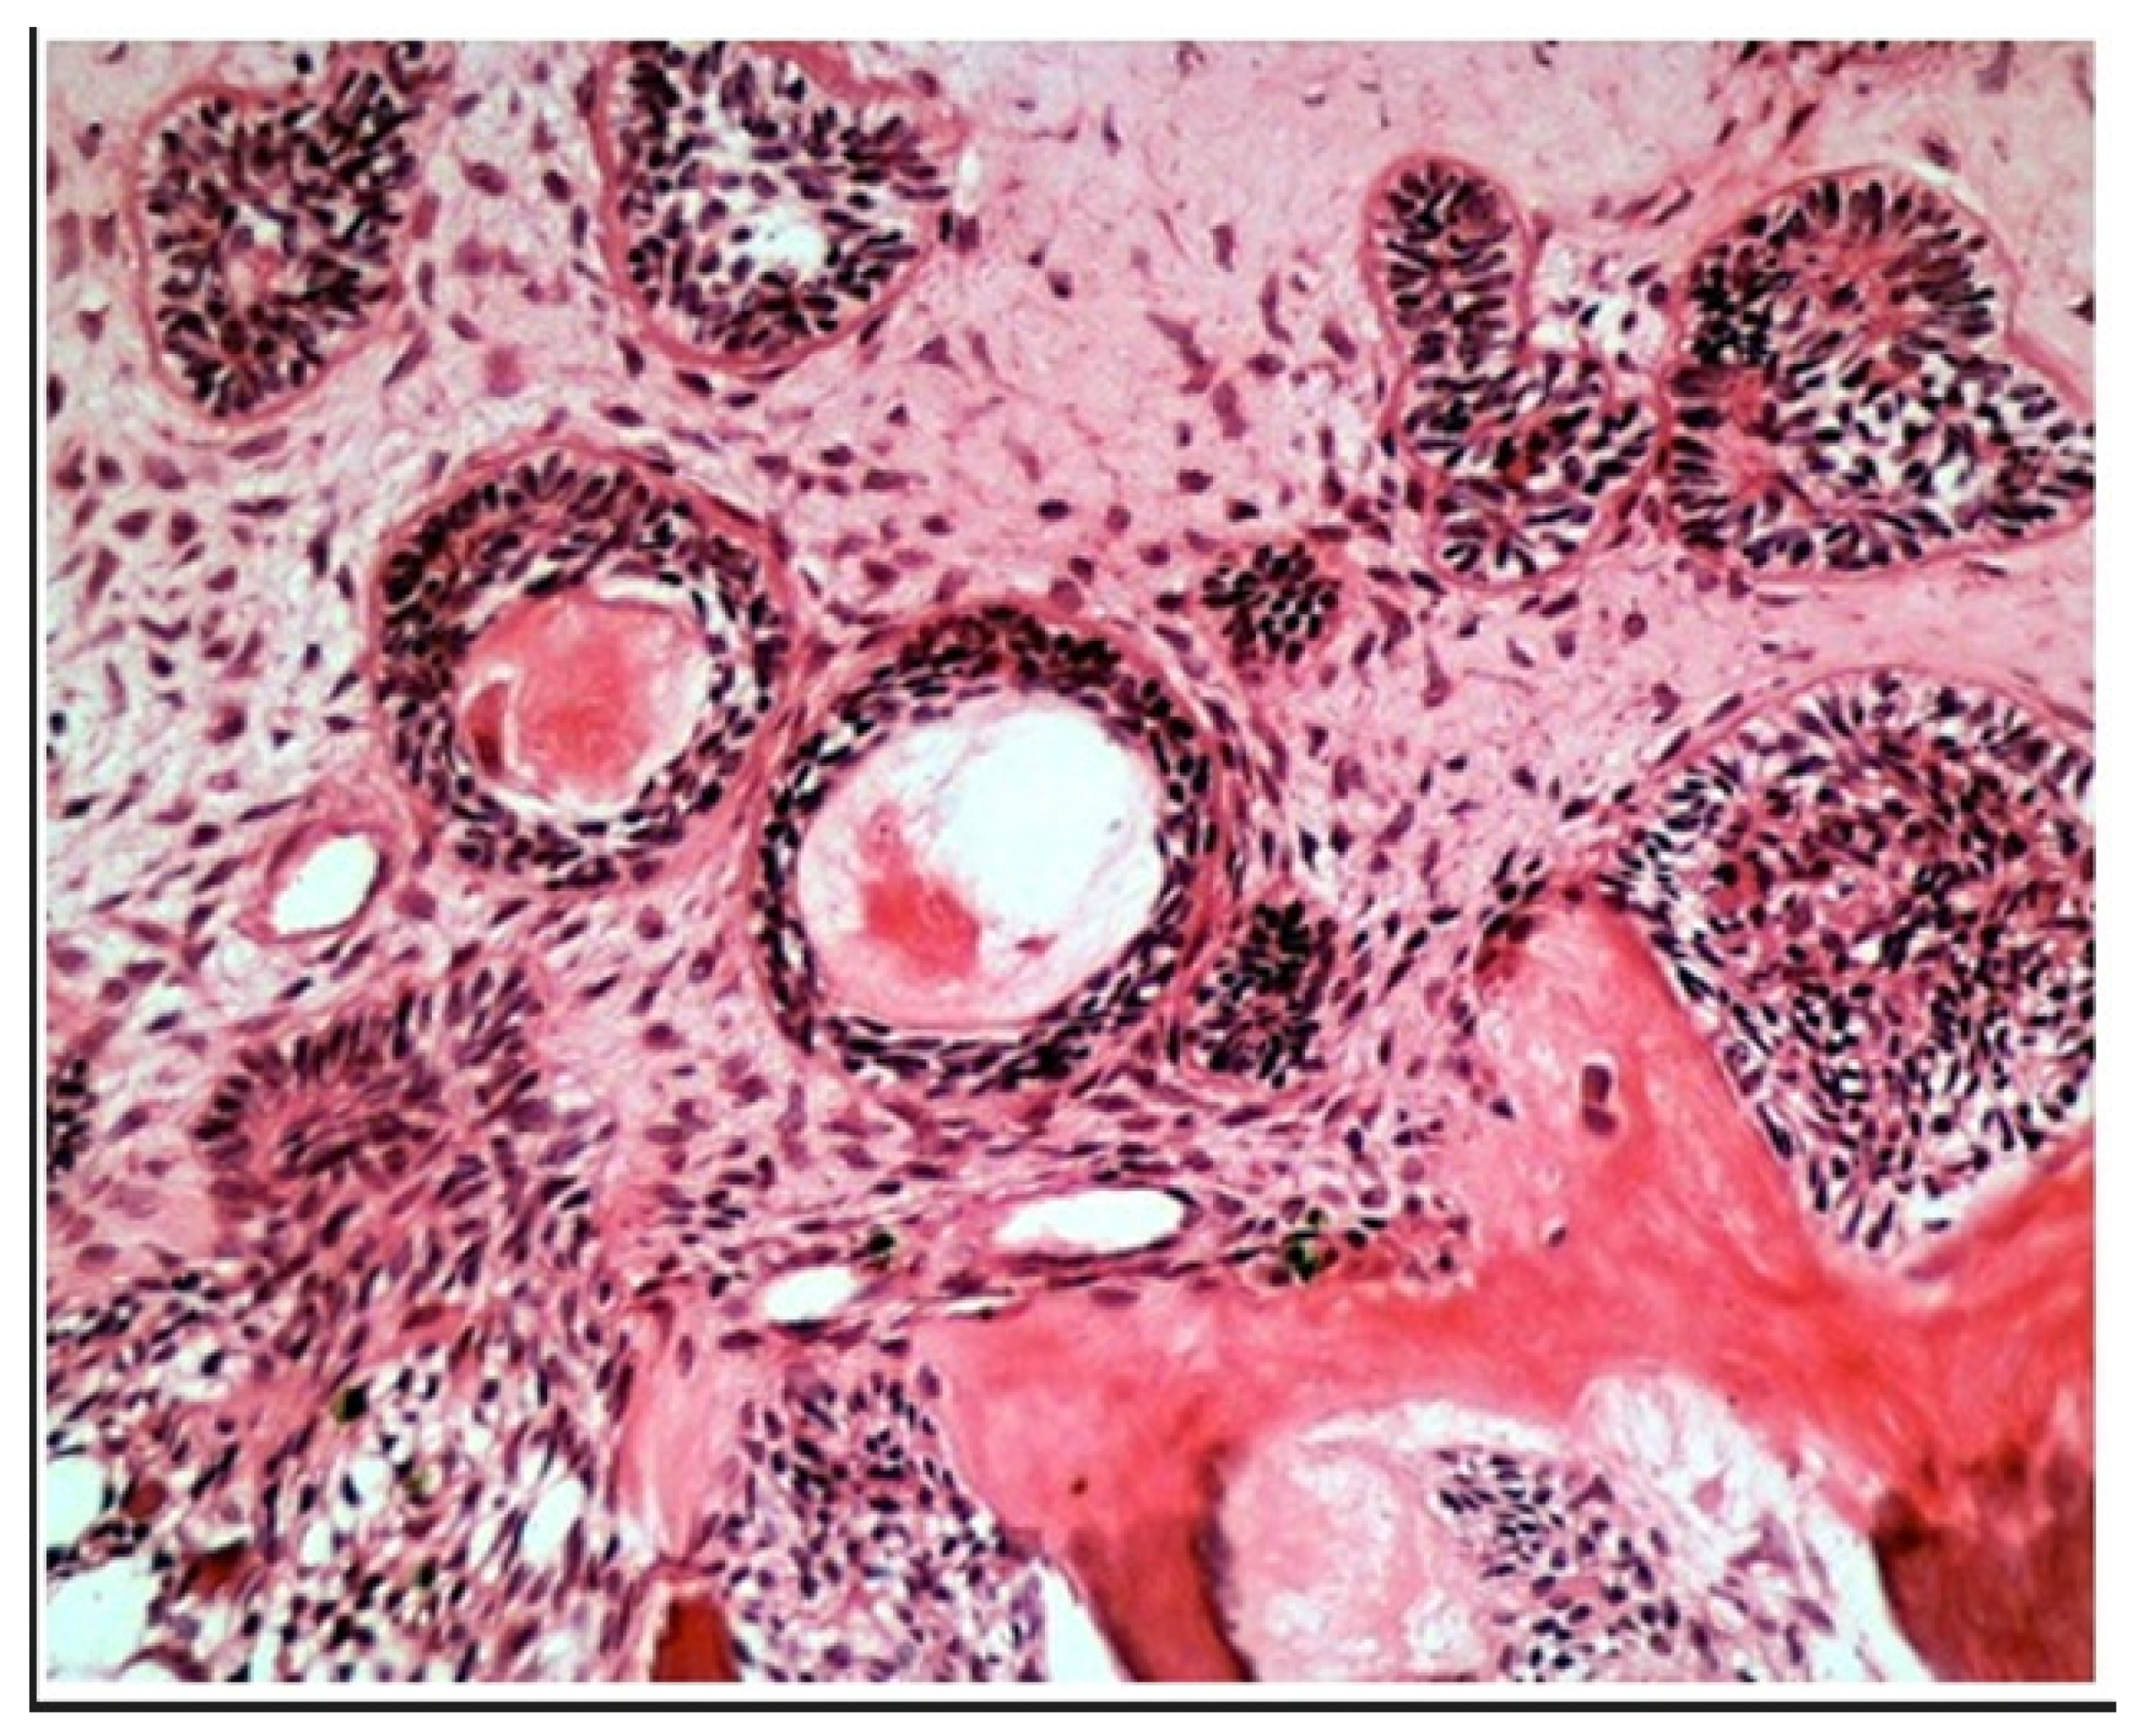

2. Case Report Presentation